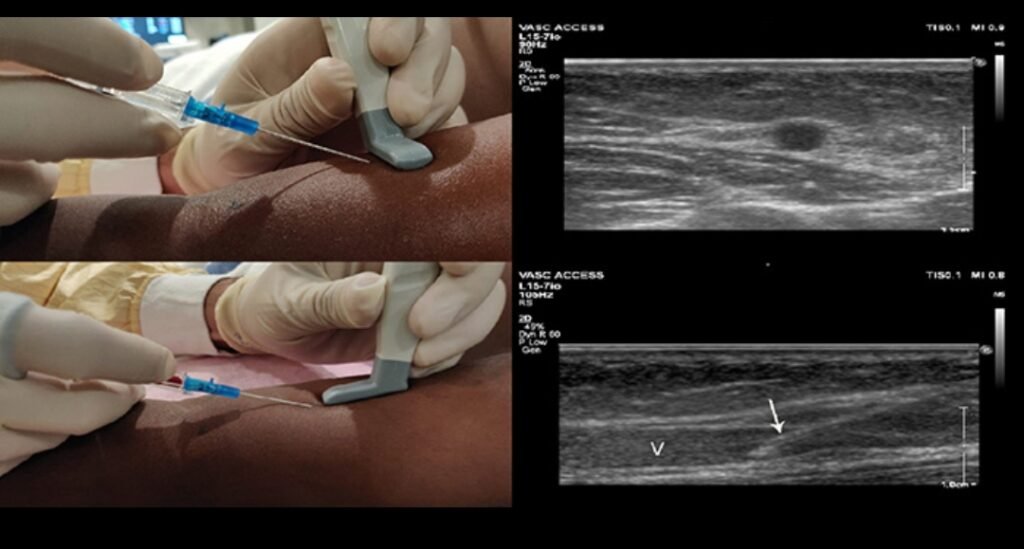

Ultrasound-Guided IV Access

Ultrasound-guided IV insertion is a game changer for DIVA patients.

Benefits

Higher first-attempt Success

reduced patient pain

Fewer complications

Faster access in emergencies

Nursing Role

Identify candidates early

Request trained personnel

Maintain aseptic technique

Monitor site closely

Many hospitals now train nurses in ultrasound-guided cannulation.Alternative Vascular Access Options